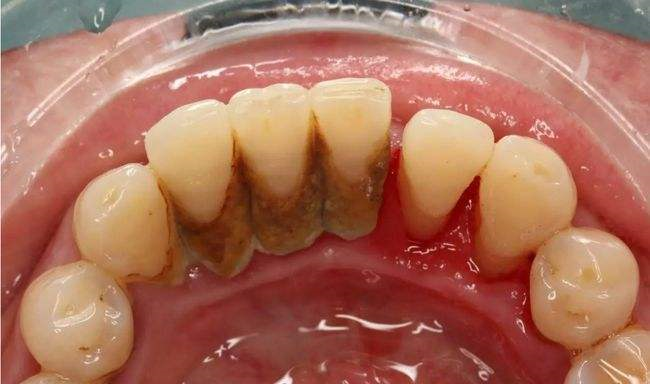

其次還會(huì)有牙周袋的形成,如果是沒問題的情況下,比較健康的牙齦齦溝深度是不會(huì)超過2mm,如果是已經(jīng)超了兩毫米那么這就是牙周袋,牙周袋的形成,在這種情況下就足以說明牙齦炎已經(jīng)發(fā)展到了牙周組織上了,促使牙周組織的感染會(huì)深入,慢慢的膿性分泌物就會(huì)從牙周袋冒出來,牙周炎的主要癥狀之一就是牙齦萎縮,但是一般我們是察覺不到的,在長(zhǎng)時(shí)間的在大量牙石壓迫刺激牙齦下,就會(huì)產(chǎn)生齦緣外形出現(xiàn)水平式的退縮癥狀。